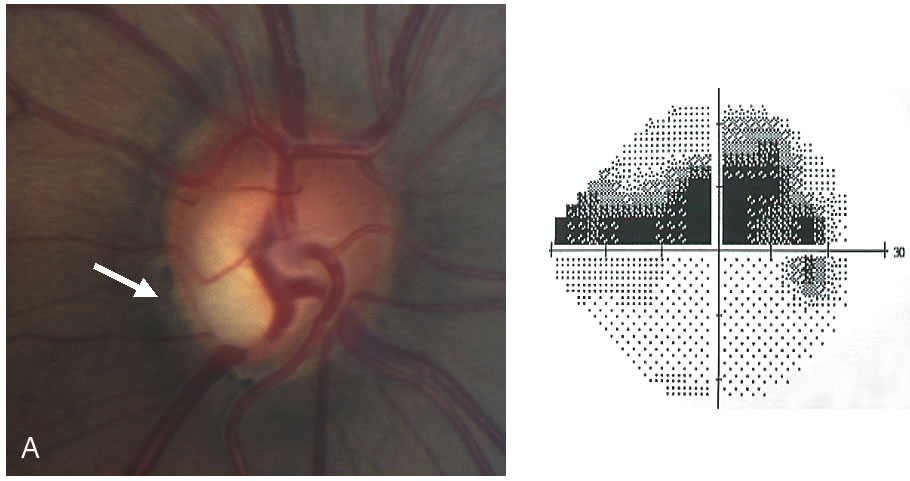

Stereometric parameters of optic nerve head topography are generated relative to the reference plane and include rim area, rim volume, cup area, cup volume, cup-to-disc ratio, mean RNFL thickness, and RNFL cross-sectional area. Parameters independent of the reference plane include mean and maximum cup depth, height variation contour, and cup shape measure (the statistical third moment of the distribution of all cup depth measurements). A characteristic sign in normal discs is the configuration of the contour line height display that demonstrates a double hump pattern corresponding to the thicker distribution of nerve fibers along the superior and inferior poles of the ONH (Fig. 4). Glaucomatous structural damage is characterized by a reduction of parameters that describe rim structures (area, volume) and indicate tissue loss (cup shape measure, cup volume, cup-to-disc ratio, cup steepness). As shown in Figure 5, glaucomatous alterations are typically associated with an asymmetrical or diffuse flattening of the contour line, or localized depressions corresponding to disc notches.